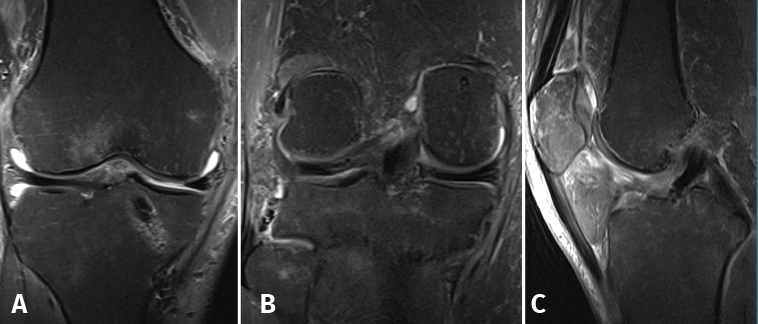

Magnetic resonance imaging (MRI) revealed multiple contusion edema zones with severe partial rupture of the ACL and grade I-II lesion of the PCL, with normal insertion at distal level (Figure 3A). In addition, proximal distension of the medial collateral ligament (MCL) and lateral collateral ligament (LCL) was observed, together with damage to the external meniscus posterior root (LaPrade type 4) (Figure 3B) associated to fracture of the external tibial plateau and deinsertion of the internal meniscus posterior root (LaPrade type 5) (Figure 3B) with meniscal extrusion (Figure 3C).

Figure 3. Magnetic resonance imaging study showing post-contusion edema of the tibia, with rupture of the anterior cruciate ligament. The posterior cruciate ligament appears correctly inserted in the sagittal view (A); the coronal view shows a radial lesion of the external meniscal root and bone avulsion with a bone fragment of the external root (B), causing extrusion of the internal meniscus (C).